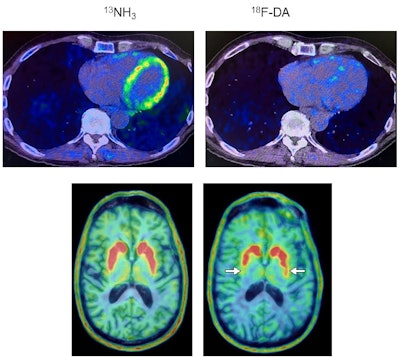

Heart and brain PET scans from a study participant who developed Parkinson’s disease support a “body first” progression. The top pair of PET scan images show low F-18 dopamine-derived radioactivity in the heart (right, with N-13 ammonia PET scan on left). Later, brain scans showed a loss of dopamine-producing neurons and the individual developed symptoms of the disease. Image courtesy of the National Institutes of Health.

In the present study, 34 people at risk for Parkinson’s underwent cardiac F-18 dopamine PET scans every 18 months for up to about 7.5 years, or until they were diagnosed with the disease. Participants had three or more Parkinson’s risk factors, which included a family history of the disease, loss of sense of smell, dream enactment behavior, and symptoms of orthostatic intolerance, such as light-headedness upon standing.

Out of nine individuals with low cardiac F-18 dopamine-derived radioactivity at their first scan, eight were diagnosed later with Parkinson’s or Lewy body dementia, according to the findings.

Additionally, only one out of 11 participants with normal initial radioactivity developed a central Lewy body disease. All nine participants who developed a Lewy body disease had low radioactivity before or at the time of diagnosis, the researchers found.